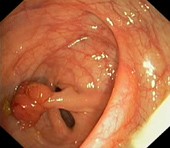

Полип |